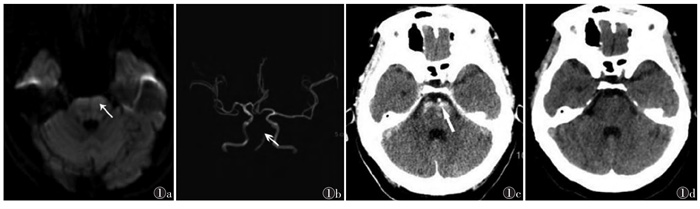

| 注:患者,女,56岁,意识不清,四肢无力5 h余入院。图 1a为术前DWI,示脑干片状高信号(箭头);图 1b为术前MRA,示基底动脉部分闭塞(箭头);图 1c为脑动脉取栓术后即刻CT,示脑干片状高密度影(箭头),边缘模糊,CT值约55 HU,周围脑组织未见肿胀,邻近脑池未见变窄;图 1d为术后第2天复查CT,示高密度影消失;此例为脑干对比剂溢出 图 1 Ⅱ型A组急性缺血性脑卒中MRI及CT图像 |